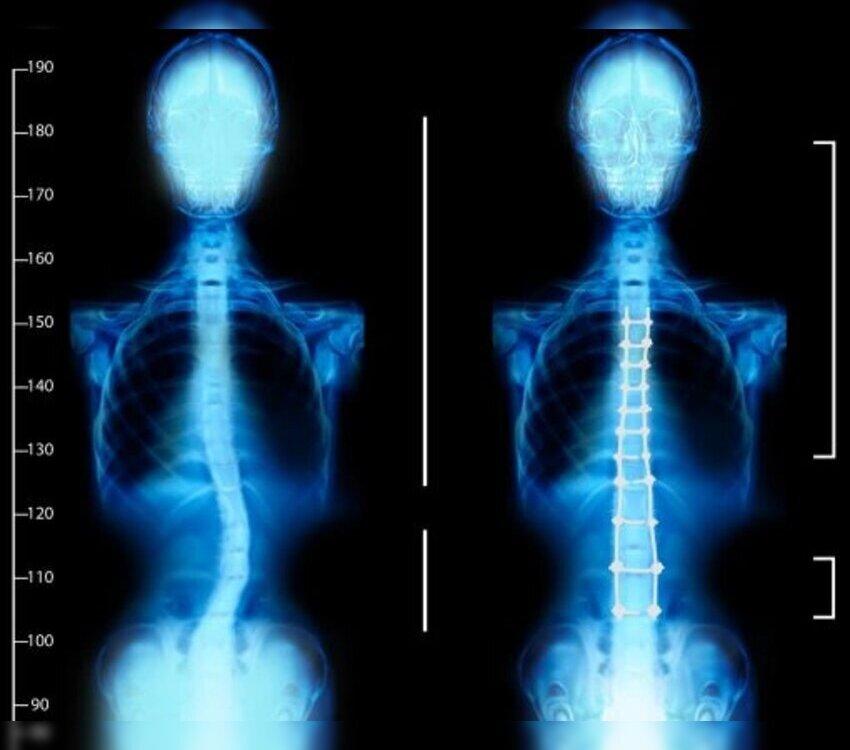

For patients with significant spinal curvature or progressive scoliosis, surgery may be recommended. Synapse Spine specializes in minimally invasive techniques, such as spinal fusion and deformity correction, which can drastically improve spinal alignment, reduce pain, and enhance mobility.

The treatment process starts with a comprehensive diagnosis, including physical exams and imaging tests, to assess the severity of scoliosis. Patients experiencing persistent pain or difficulty in breathing due to spinal deformity are often prime candidates for scoliosis surgery. At Synapse Spine, these surgeries are performed with precision, reducing risks and ensuring quicker recovery times.